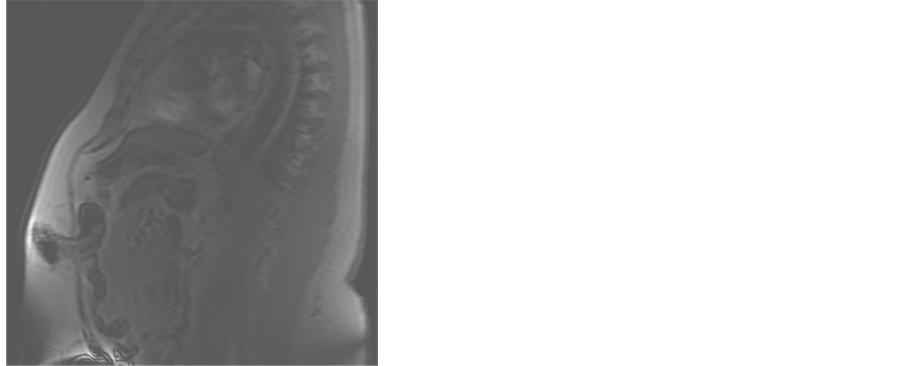

The Patient is a 62-year-old, gravida 2, para 2 woman with BMI of 43.6 kg/m2. She was not on hormone replacement therapy. Figure 1 and Table 1 summarize her clinical course. She presented with vaginal bleeding.

An endometrial biopsy revealed a grade 1 endometrial adenocarcinoma. She underwent an uncomplicated laparoscopic hysterectomy with bilateral salpingo-oophorectomy. One month postoperatively, she developed a deep vein thrombosis. She was treated with low molecular weight heparin as anticoagulation therapy. Three months after her hysterectomy, she presented with metastatic tumor in her port sites and a pelvic mass. She underwent an exploration, and fully cytoreductive surgery with excision of the pelvic tumor, upper vaginectomy, sigmoid resection, and end colostomy. One month later, she had evidence of tumor recurrence. Chemotherapy with carboplatin and paclitaxel was started. She received six cycles of chemotherapy with a complete resolution of tumor. She is currently disease-free at five months from completion of chemotherapy.